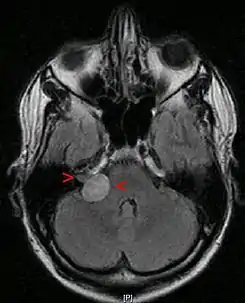

Neurinoma acústico con un tamaño de 20 x 22 x 25 mm. RMN en corte axial a nivel de globos oculares.

Resonancia magnética con contraste.